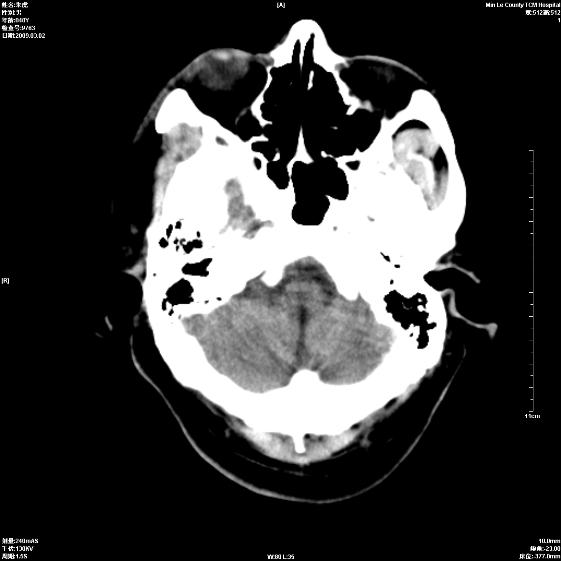

标题: CT18444:男颅咽瘤术后一月复查脑积水增多 [打印本页]

标题: CT18444:男颅咽瘤术后一月复查脑积水增多

右侧额叶局软化灶,梗阻性脑积水。

右额叶软化灶。梗阻性脑积水。

手术后改变

1、右额叶脑软化

2、脑积水

四脑室上方积水,右额叶软化灶。

1)右侧额颞部颅骨术后改变。2)右侧额颞叶脑软化灶。3)脑积水(梗阻性)。

手术后改变1、右额叶脑软化2、梗阻性脑积水。